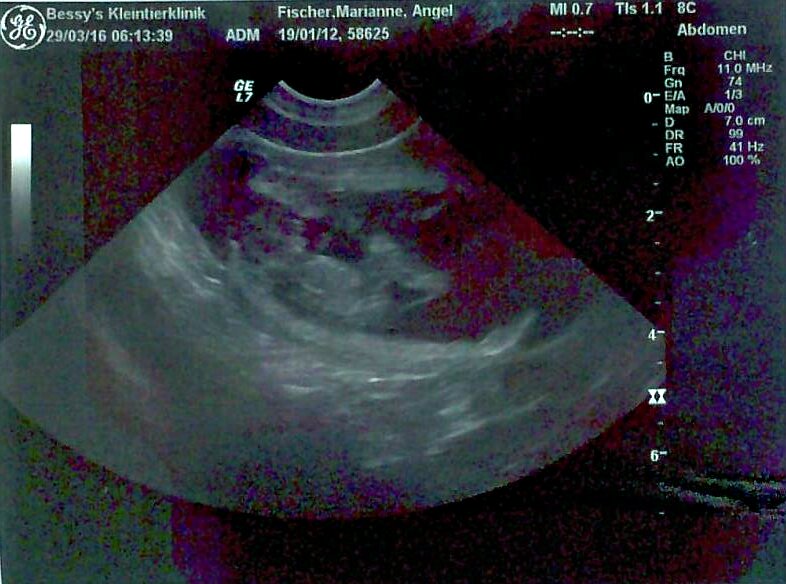

Die lange Ungewissheit hat ein Ende - Angel ist definitv trächtig! Im heutigen Ultraschall konnten wir eindeutig 8-9 Fruchtblasen erkennen. Der Q-Wurf kann kommen - ich freue mich riesig drauf!